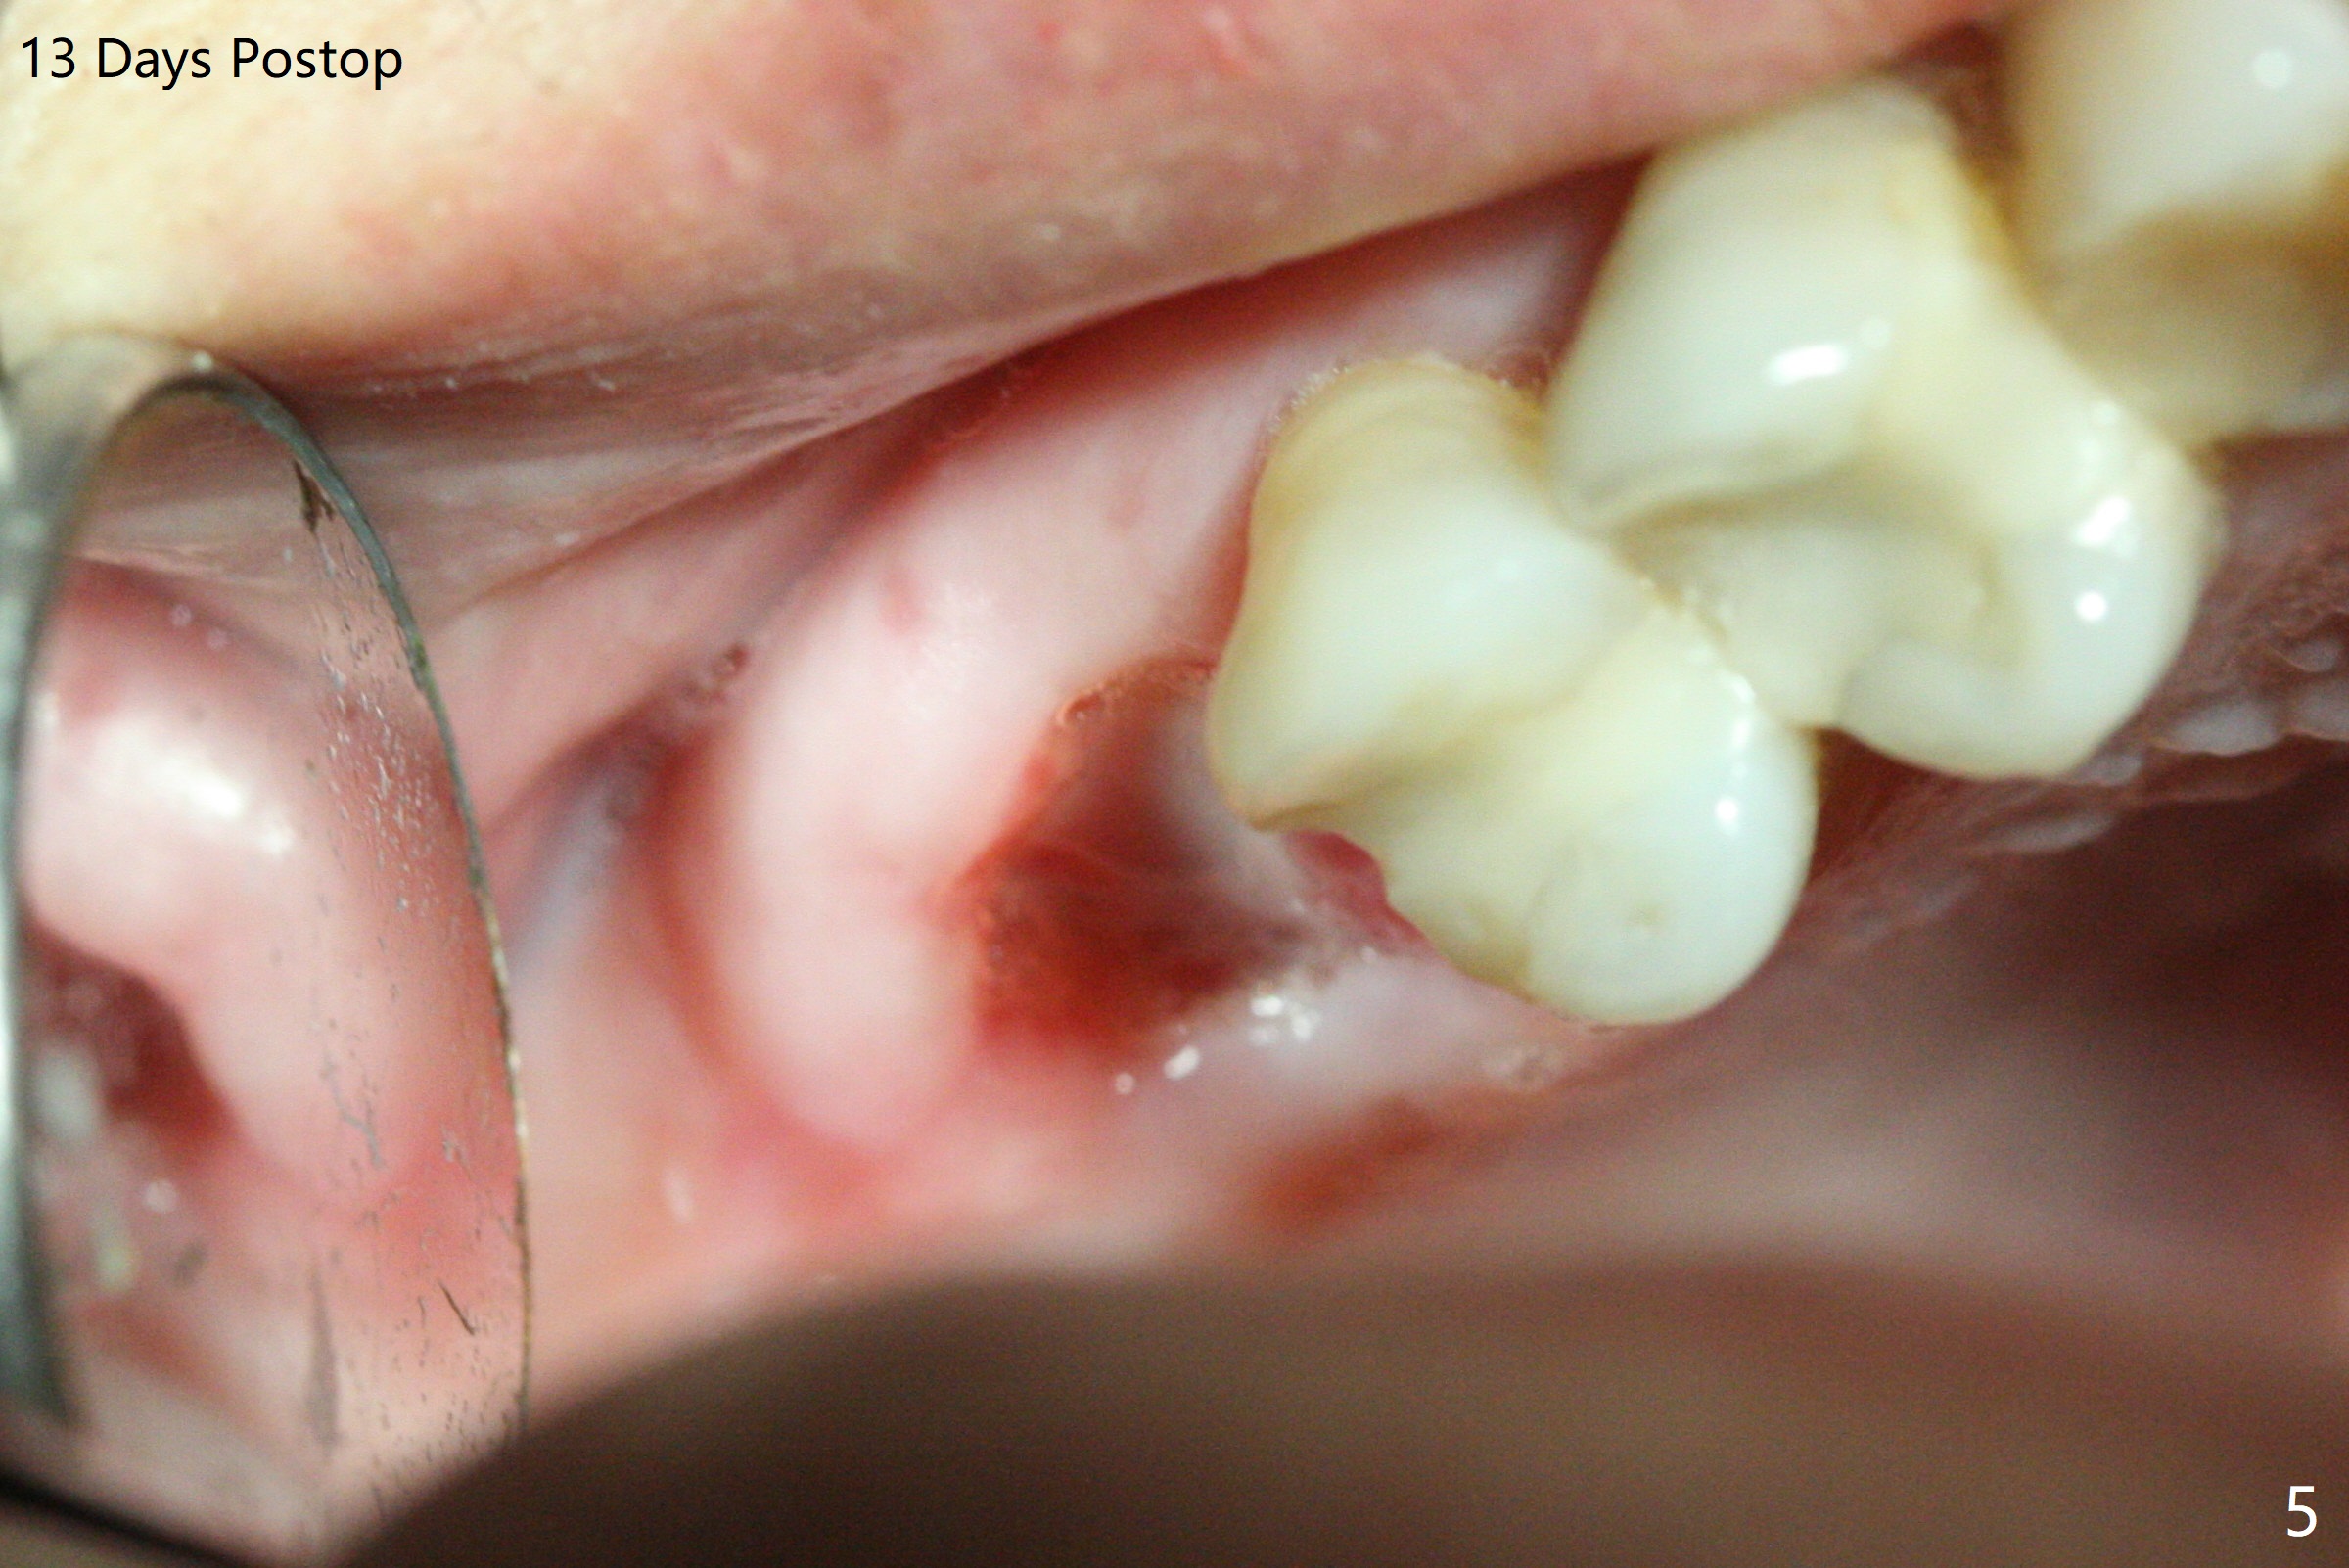

A 53-year-old woman wants to extract the tooth #3 with recurrent apical periodontitis (Fig.1). Socket preservation is conducted (Fig.2). The tooth is terminal in the arch and difficult to keep periodontal or acrylic dressing in place. To overcome the situation, a prefabricated space maintenance is placed without cementation because of its inherent fitness (Fig.3). Periodontal dressing (Fig.4 D) appears to be retained in place. The spacer is lost prematurely due to no cement, but the wound appears to be healing 13 days postop (Fig.5,6). The socket heals 3 months postop (Fig.7,8). However the ridge is narrow 19 months postop (Fig.9, as compared to that of the tooth #14 (Fig.10)).